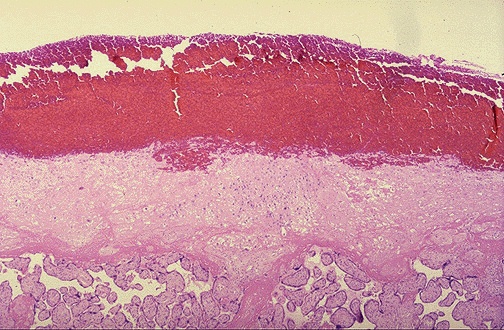

Microscopically, this abruptio placenta is seen to have extensive hemorrhage at the top of the image, at the decidual plate, with placental villi below.